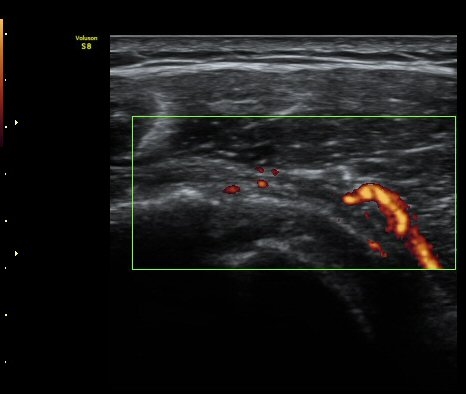

ÆÄ¿öµµÇ÷¯°Ë»ç¿¡¼­ ±Ø»ó°Ç°ú Á¡¾×³¶ÁÖÀ§¿¡¼­ ¼ö¾×Àú·ù°¡ °üÂûµÈ´Ù(±×¸² 6, 7).

±Ø»ó°Ç ¸»´ÜºÎ Á¾´Ü¸é°Ë»ç¿¡¼­ ±Ø»ó°Ç°ú Á¡¾×³¶³» ¼®È¸È­°¡ °üÂûµÈ´Ù(±×¸² 4, 5).